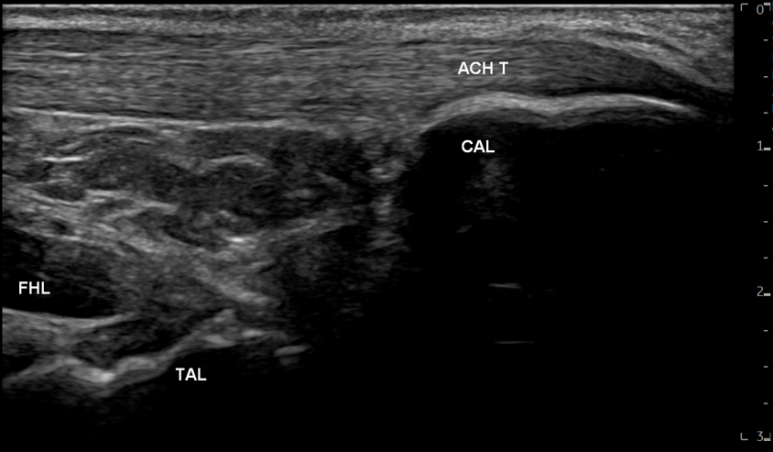

영상에서

족태양경근은 깊이에 따라

아킬레스건, 장무지굴근, 종골, 거골 등

다양한 구조물이 보입니다.

그 중에

아킬레스건(ACH T)은흰색 줄무늬 섬유 패턴으로보이는데요.